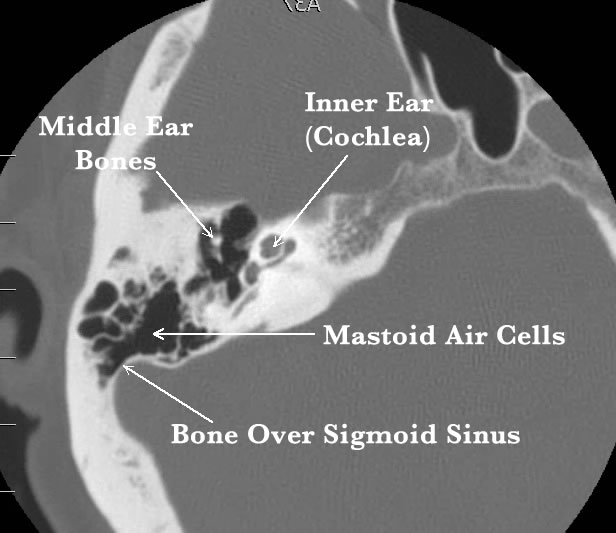

There are several radiographic imaging studies used to determine the cause of pulse-synchronous tinnitus. These studies include magnetic resonance imaging (MRI) of the brain, magnetic resonance angiography (MRA) of the brain and/or neck to evaluate arteries in the brain/neck, magnetic resonance venography (MRV) brain and/or neck for the venous system, CT temporal bones, CT angiography of the brain, and cerebral angiogram (similar to cardiac angiogram for the heart). Each of these imaging studies provides unique information. Which study, or studies, is/are used is determined by the possible cause for PST based on the individual’s history and physical exam. Sigmoid sinus dehiscence/diverticulum is best seen on a dedicated CT radiographic imaging of the ear and surrounding structures (CT temporal bones). The images below are examples of a normal sigmoid sinus (image on left) and sigmoid sinus dehiscence (image on right). [CT: White structures = bone; Black = air; Gray = soft tissue]